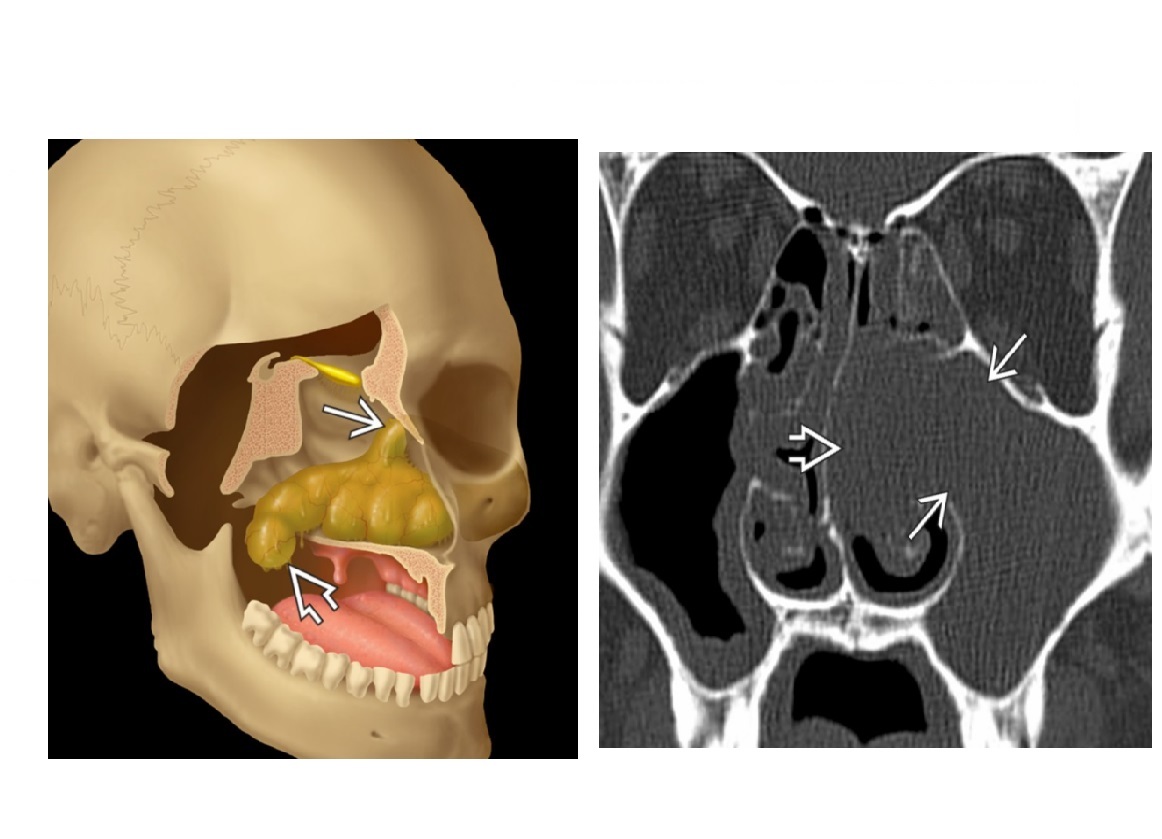

Complete opacification of the maxillary sinus, peripheral enhancemen, expanded sinus with smooth remodeling of walls?

Mucocoele

Nb - Ostium of given sinus is occluded thus complete opacification.

*- Doesn’t extend beyond the cavity. *

- **Expands cavity and can cause bone thinning. **

Associated with* CF and prior trauma*

Peripheral enhancment allows differentiate from neoplasm

Low attenuation mass in the sinus that expands the cavity and extends into the meatus ?

Antrochonal polyp/Solitary Sinonasal Polyp

*Nb - T2 bright and also peripheral enhancement. *

Typically doesn’t completely opacify the sinus

Solitary ‘dumbell shaped-‘ polypoid mass fills maxillary antrum, then spills through enlarged maxillary ostium and infundibulum or accessory ostium into nasal cavity